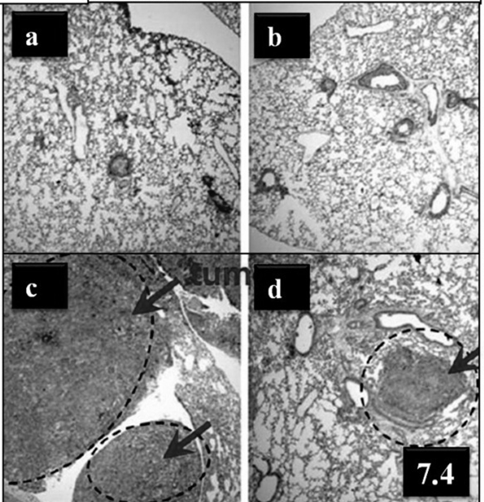

Fig. 7.4: Histology of lung tissues in the four study groups at 4 weeks after B16F10 cell implantation (5 X105 ea, 0 day) and/or pulmonary administration of Dox PLGA MPs (5, 14 day). (a) age-matched treatment naive control mouse; (b) Dox PLGA MP administered mouse; (c) B16F10-implanted mouse; and (d) B16F10-implanted and Dox PLGA MPs administered mouse [27]

In a study performed by Hershey et al. treated 24 anesthetized dogs with developed stages of spontaneous primary lung cancer or metastases with doxorubicin or paclitaxel aerosols administered twice weekly [178]. Tumor suppression was achieved in 25% of dogs with significant tumors without any systemic side effects usually associated with i.v. administration of these drugs and without pulmonary toxicity in the dogs treated with paclitaxel. In a studies demonstrated by Ajay Gautham et al. clearly explained the aerosol delivery of PEI–p53 complexes which inhibits B16-F10 lung metastases through regulation of angiogenesis [179]. Insoo Kim et al. in 2012 and his group fabricated doxorubicin-loaded highly porous large PLGA microparticles for the treatment of metastatic lung cancer via inhalation and they found Dox PLGA MPs have great potential as a long-term inhalation agent for the treatment of lung cancer (fig 7.1 & 7.4) [27]. At present, the study of inhaled doxorubicin combined with platinum-based therapy by Gregory et al. is in the phase I/II clinical trial for advanced NSCLC [180].